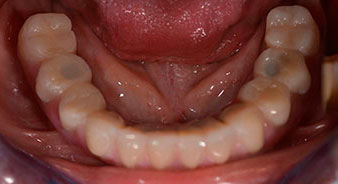

The impression and bite registration were then performed so that the dental technician could begin producing the provisional restoration immediately. This was then screwed in on the same day (Fig. 17 and 18).

Implants

Following the time required for the osseointegration, the final impression of the implants could be performed and the final denture produced accordingly (Fig. 19 and 20). At this point, the dentist and patient were able to decide together whether to use a ceramic or acrylic veneer and a zirconium or metal framework. In this case, Dr. Pascu’s team decided on an acrylic veneer based on the unclear prognosis for the maxillary dentition and the fact that tooth 24 is elongated. This type of veneer is generally considerably easier to adapt and can thus be subsequently altered to reflect the new situation in the maxilla.

Osseointegration